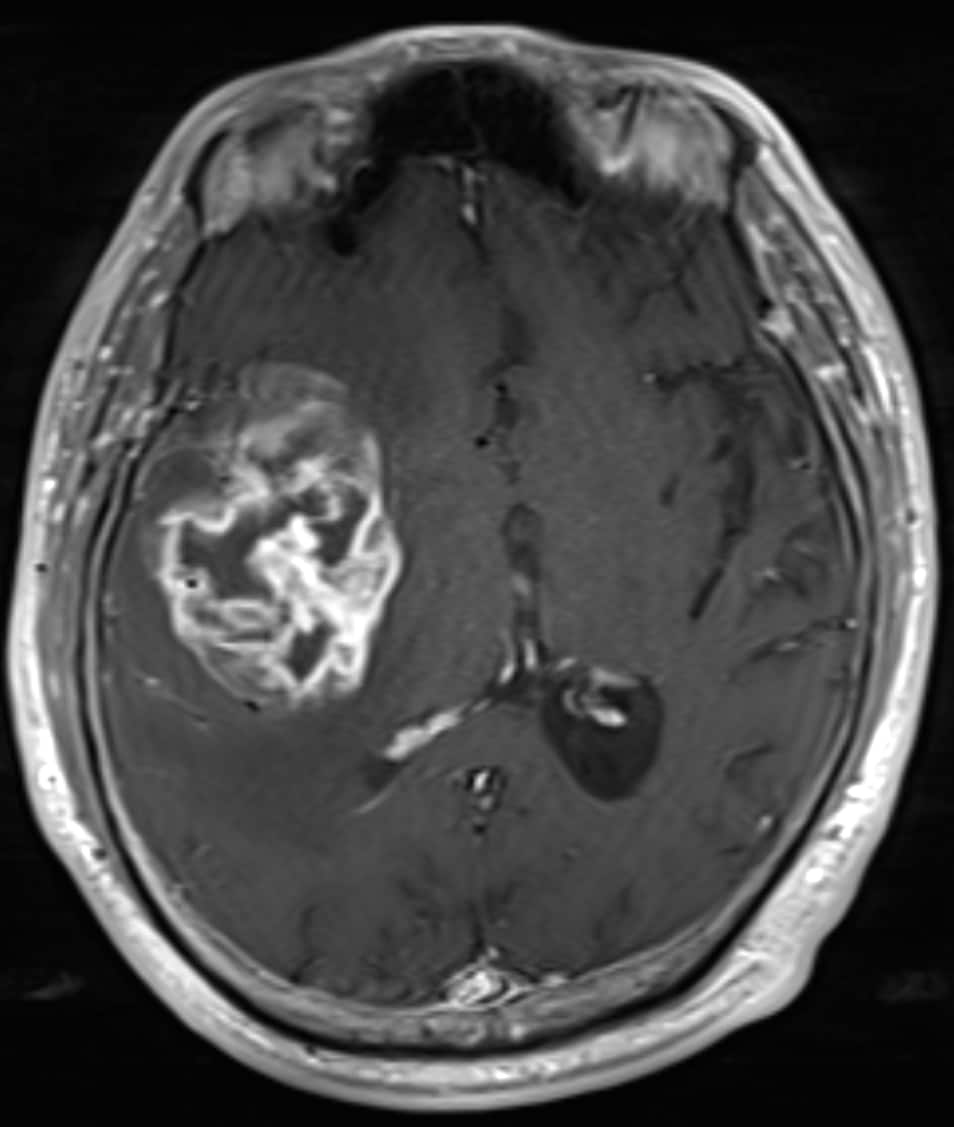

主訴は左下肢の脱力、歩行困難。右島回に5cm大の腫瘤を指摘され、膠芽腫が疑われた。術前の血管評価のため頭部CTA、CTVを施行した。

手術が施行され、glioblastoma, IDH-wild type, CNS WHO grade 4と診断された。現在、放射線化学療法中である。

当該疾患の診断における造影CTの役割

島回部のglioblastomaの術前CTAにおいて、手術中の予期せぬ血管損傷の回避、ひいては術中出血や虚血性合併症のリスク低減のために中大脳動脈や穿通枝など主要血管を可視化する必要がある。血管と腫瘍の位置関係を把握することで、腫瘍をできる限り摘出しつつも神経機能を温存する戦略を立てることができるようになる。隣接する基底核部は錐体路や感覚路と近接するため、摘出範囲の判断のために術前の血管情報が不可欠である。

また、術前の血管画像をナビゲーションシステムに統合することで、リアルタイムに血管・神経の位置を確認しながら手術が進められ、より手術の安全性を高めることができる。膠芽腫は浸潤性が強いため、血管を温存しながらも腫瘍を完全に摘出することが困難であることが多く、機能温存と腫瘍制御の最適なバランスのために術前の詳細な血管描出が重要となる。